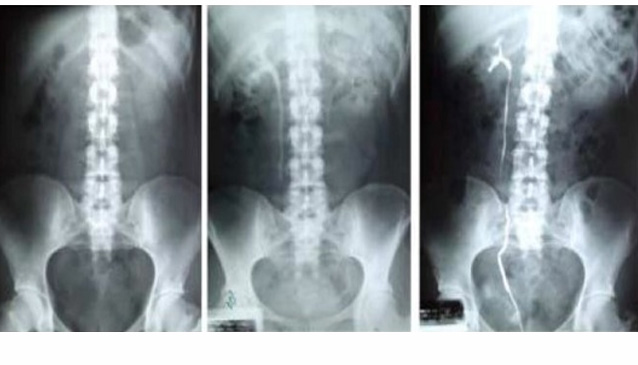

En la pielografía ascendente (de abajo para arriba) se introduce un cateter en el cual se inserta en la union del uretero a la vejiga y se inyecta medio de contraste que "pinta" el uretero hacia arriba hasta llegar al riñon (el caliz).

En la pielografía descendente se inserta medio de contraste intravenoso, el cual es filtrado por los riñones y excretado a través del riñon al uretero hasta la vejiga.

El radiólogo puede encontrar el bloqueo observando las imágenes de rayos X. La tintura de contraste no podrá avanzar o puede tardar en pasar por el riñón si usted tiene un bloqueo. También es posible que necesite esta prueba para evaluar los riñones o uréteres antes o después de una cirugía. Si usted tiene un bloqueo, el cirujano puede usar un tubo especial (stent ureteral) para que la orina pase alrededor del bloqueo o puede colocar un tubo en un riñón (catéter de nefrostomía) para aliviar la obstrucción. Es posible que su proveedor de atención médica tenga otras razones para recomendar una pielografía descendente.